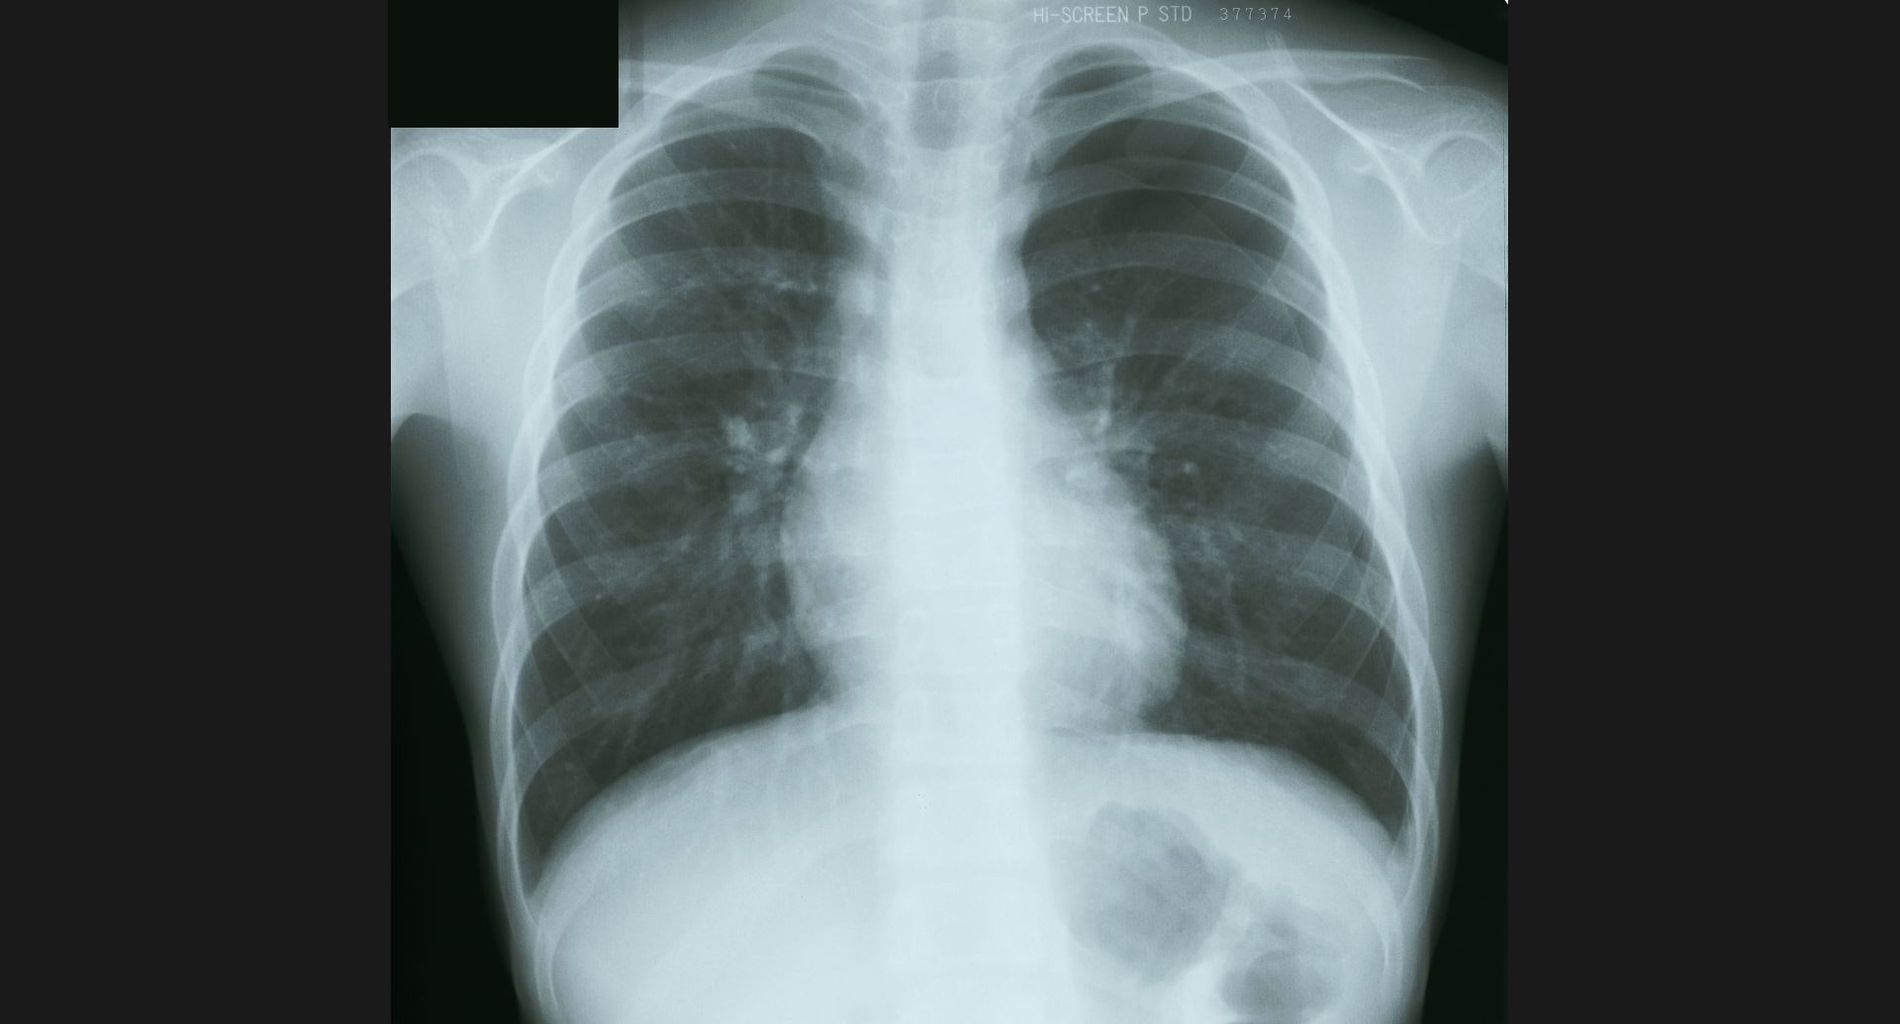

【愕然】肺気胸とかいう病気になった結果・・・・・・